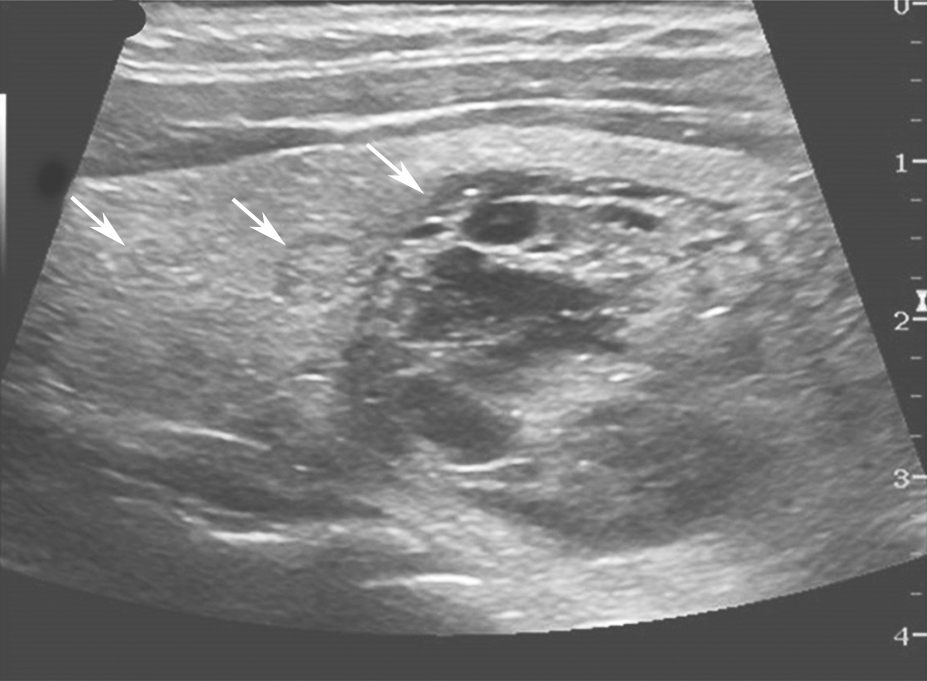

(十四)甲状腺癌淋巴结转移

典型甲状腺癌淋巴结转移的超声征象包括:类圆形、淋巴门结构消失、皮质内团状高回声区、微小钙化灶、囊性变,不规则血流信号等(图19,图20)。淋巴门结构消失这一特征的灵敏度高,但特异度较低;而微钙化及囊性变等特征的特异度最高,但灵敏度较低。

,实性成分偏心分布,内可见点状回声,手术证实为颈侧方淋巴结转移.jpg)

图19颈右侧横切面:甲状腺乳头状癌患者,颈部侧方Ⅳ区可见囊实性混合回声(箭头所示),实性成分偏心分布,内可见点状回声,手术证实为颈侧方淋巴结转移

,部分淋巴结内可见团状高回声,手术证实为颈侧方淋巴结转移.jpg)

图20颈左侧纵切面:甲状腺乳头状癌患者,颈部侧方Ⅳ区淋巴结皮髓质分界不清(箭头所示),部分淋巴结内可见团状高回声,手术证实为颈侧方淋巴结转移

超声对于中央组淋巴结转移敏感度只有50%左右。超声对于颈侧方淋巴结转移的敏感度较高,可达90%左右。超声颈部淋巴结有无异常对甲状腺手术方式选择非常重要,因此,术前超声除了对可疑淋巴结进行分区定位外,还应尽可能描述颈侧方淋巴结与颈部大血管的关系,必要时体表标注。